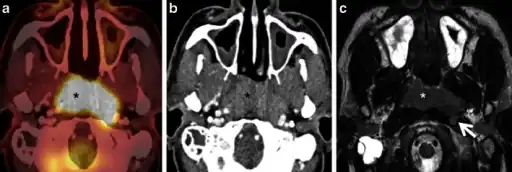

Nasopharyngeal carcinoma, also known as nasopharyngeal cancer, is classified as a malignant neoplasm, or cancer, arising from the mucosal epithelium of the nasopharynx, most often within the lateral nasopharyngeal recess or fossa of Rosenmüller (a recess behind the entrance of the eustachian tube opening). The World Health Organization classifies nasopharyngeal carcinoma in three types, in order of frequency: Non-keratinizing squamous cell carcinoma; keratinizing squamous cell carcinoma; and basaloid squamous cell carcinoma.[16] The tumor must show evidence of squamous differentiation, with the non-keratinizing type (also known as lymphoepithelioma) the tumor most strongly associated with Epstein-Barr virus infection of the cancerous cells.[17]

Staging of nasopharyngeal carcinoma is based on clinical and radiologic examination. Most patients present with Stage III or IV disease.

Stage I is a small tumor confined to nasopharynx.

Stage II is a tumor extending in the local area, or that with any evidence of limited neck (nodal) disease.

Stage III is a large tumor with or without neck disease, or a tumor with bilateral neck disease.

Stage IV is a large tumor involving intracranial or infratemporal regions, an extensive neck disease, and/or any distant metastasis. [18]